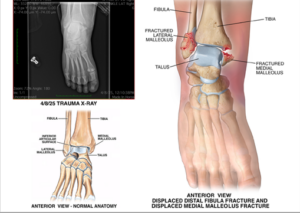

Her injuries included:

- Multiple fractured bones in her face, including left orbital and left maxillary fractures

- A left femur fracture, requiring surgery and insertion of a metal rod

- A right ankle injury, also requiring surgery and insertion of hardware